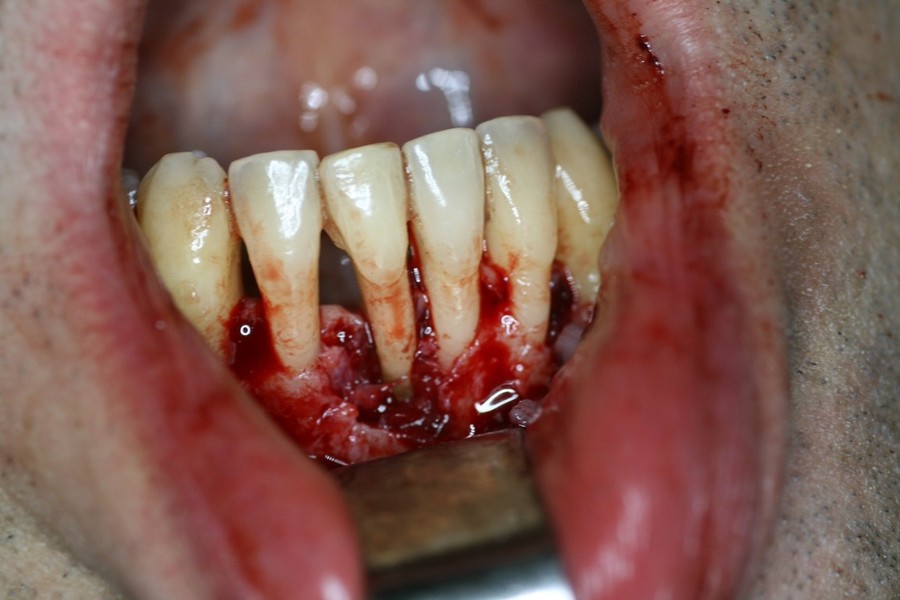

Rigenerazione Gravi difetti parodontali

rigenerazione grave difetto parodontale a carico una intera emiarcata